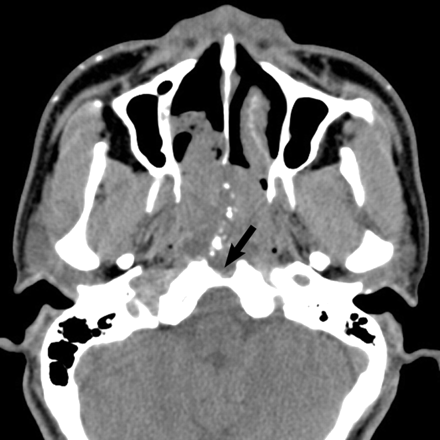

CT of the extraosseous chordomas showed a lobular soft-tissue mass centered in the nasopharynx with scalloping of the adjacent anterior margin of the clivus in all cases (Fig 1). All (5/5) lesions show lytic changes with a subtle sclerotic margin. Five of 5 lesions were heterogeneous but hypoattenuated relative to adjacent muscle. Two of the 5 lesions demonstrated dystrophic calcifications within the tumor matrix (Fig 2). In 3 of 5 cases, a well-defined tract was seen extending into the midline clivus, thought to represent the medial basal canal (Fig 2). A narrow zone of transition with a sclerotic margin was seen around the tract in all cases.

A 56-year-old man presented with a 2-year history of nasal obstruction. Axial noncontrast CT scan shows dystrophic calcification and a midline sinus tract (arrow), which can help with the preoperative diagnosis of extraosseous nasopharyngeal chordoma. This sinus tract is thought to represent tumor extending into the medial basal canal.